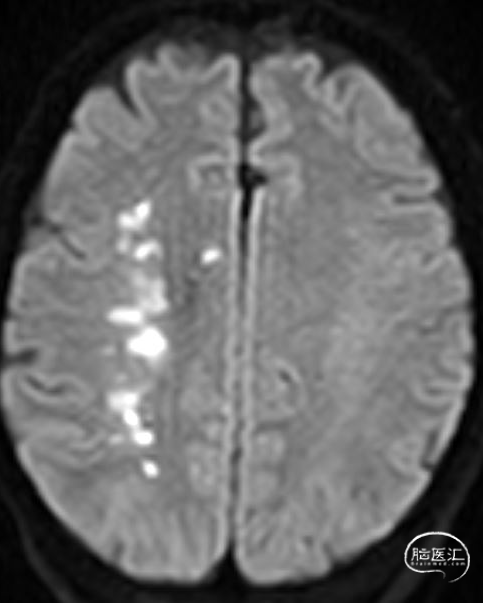

02、术前影像

为进一步评估梗死大小和颅内情况,磁共振显示颈内动脉闭塞,小的核心梗死。